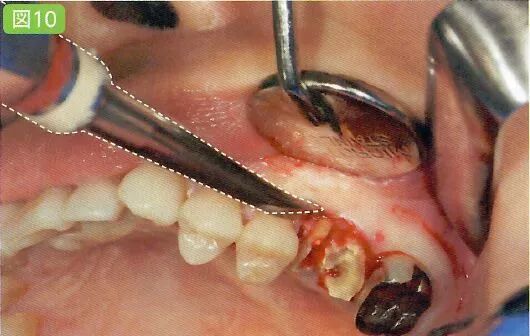

残根的拔除

通过拔除残根,将不需要削除牙槽骨,牙槽骨和牙根痊愈,也不会出现牙根膜腔根部肥大,根弯曲的症状。必然的牙槽骨和牙根之间是切削位置。留心同一部位的吸引。

预防水珠飞散

将牙骨、牙冠、牙根置于清晰的视野之下智齿/残根,无论是处于哪一种情况之下,在进行牙骨切削时为了防止牙骨被灼伤,一定要充分注水。注水时在水珠迸溅的地方放上吸唾器,以减少水珠乱飞的情况(图9)在主治医生停下手中动作时利用吸唾器吸引口腔内的水。若是使用涡轮机或者引擎产生的注水量较多,可以换用口腔用吸唾器。

牙冠分割和骨削除的方法根据主治医生的不同也会有所差别,但若是能完成基本出血、注水、削除片等部分的吸引的话,术野的保证也会变得更加容易。

完成出血点、注水和削除片的吸引,以保证术野的清晰度。